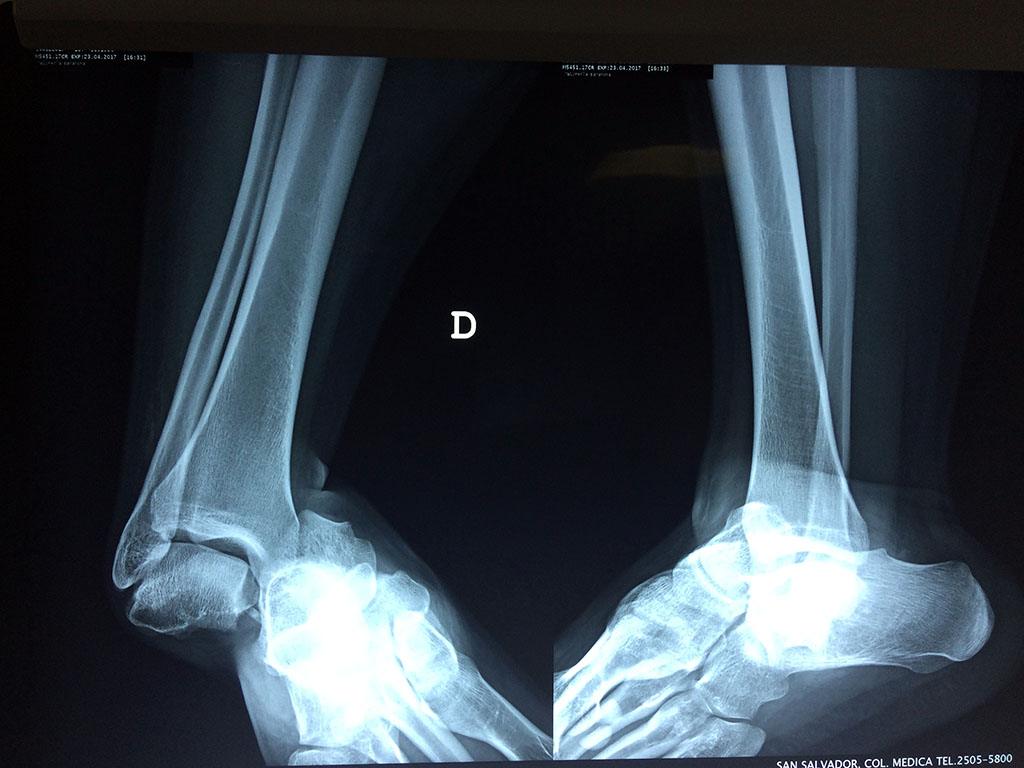

Una fractura de tobillo es la rotura de uno o más de los huesos del tobillo. Estas fracturas pueden ser:

Algunas fracturas de tobillo pueden requerir cirugía si:

- Los extremos de los huesos están desalineados entre sí (desplazados).

- La fractura se extiende hasta la articulación del tobillo (fractura intra-articular).